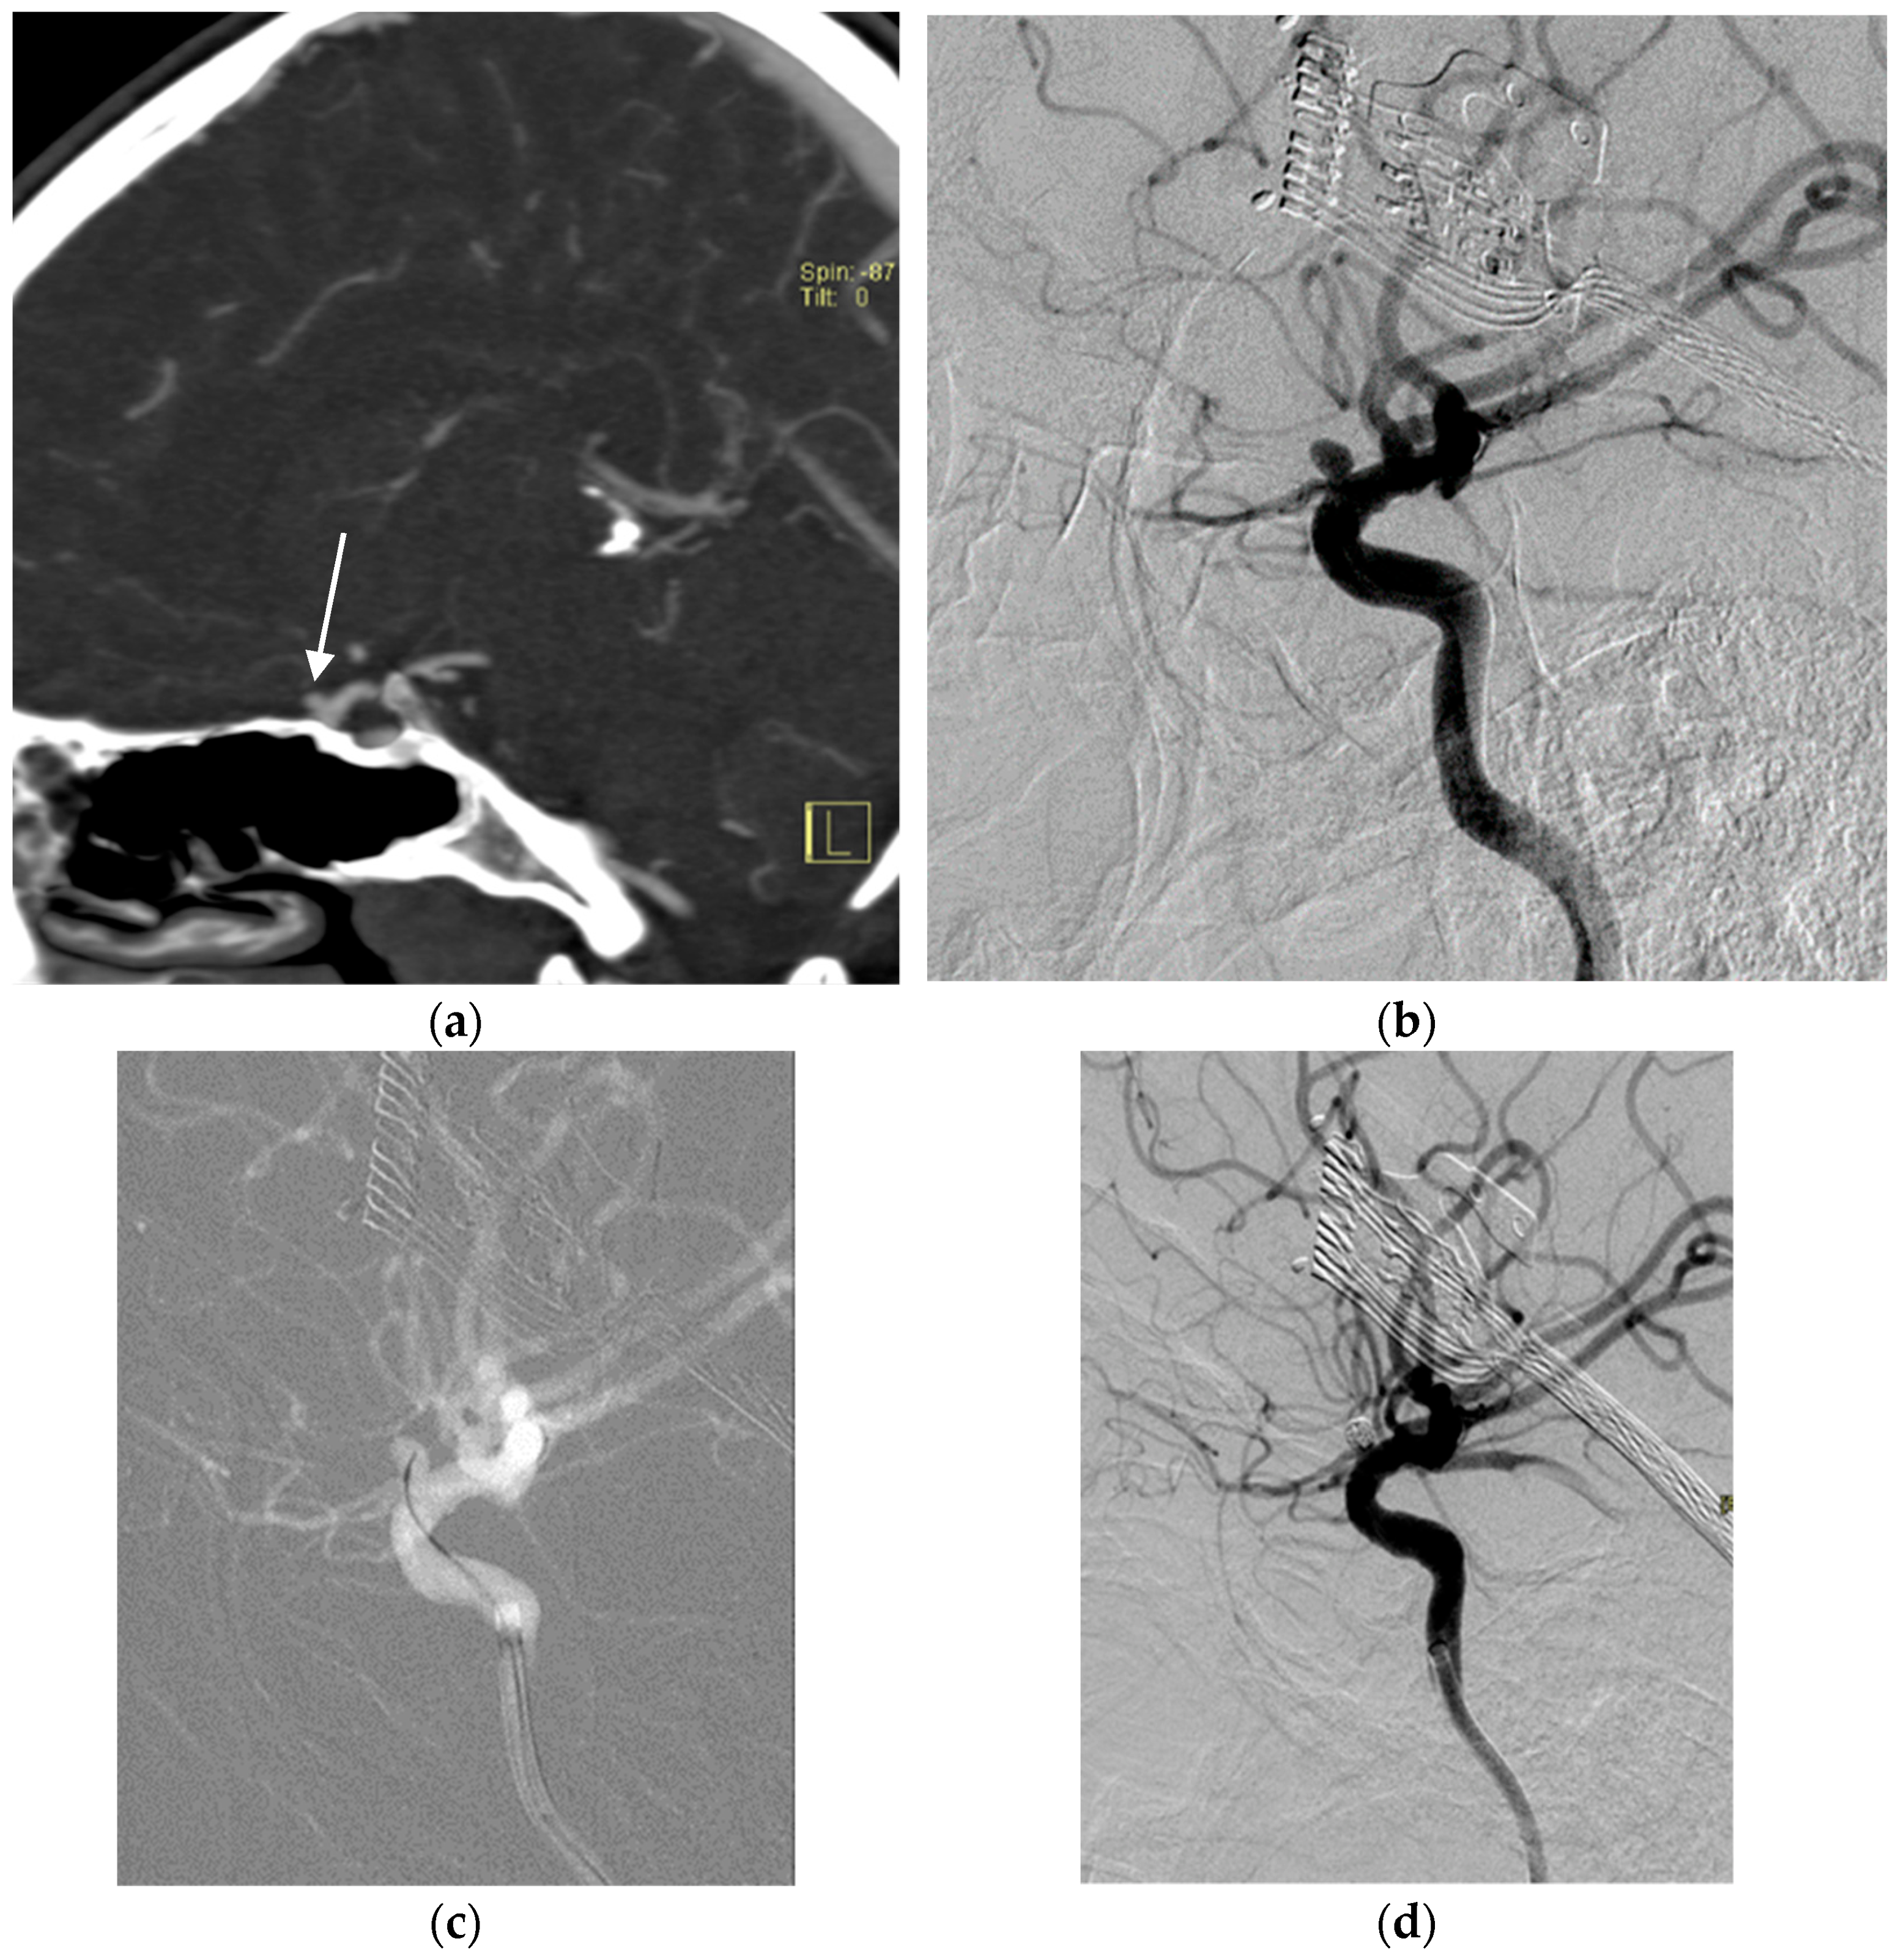

2.3. Aneurysms